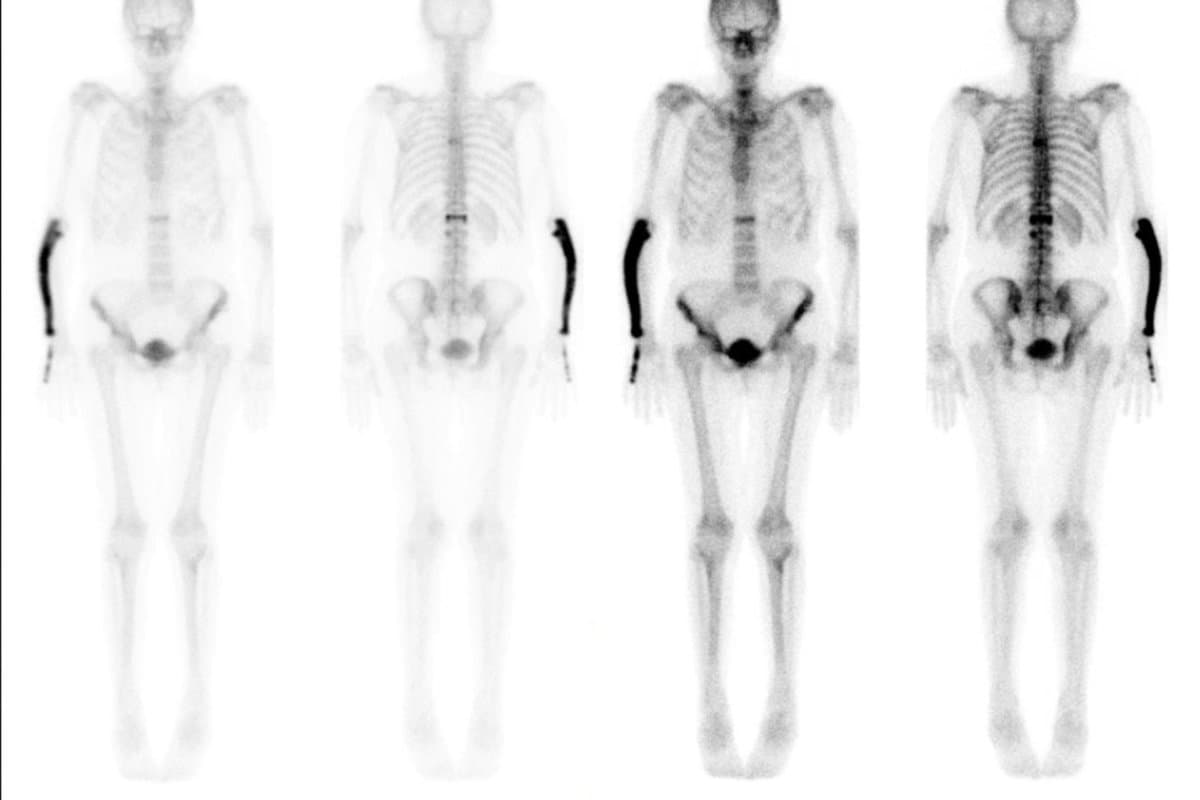

Festgestellt wird die Erkrankung meist mittels einer Knochenszintigraphie.

Zu Beginn der Studie wurde bei allen Teilnehmern ein Knochenscan durchgeführt, um sie auf Knochenläsionen zu untersuchen. Ausserdem wurden sie auf den Knochenresorptionsmarker C-terminale Telopeptide des Typ-I-Kollagens (CTX) und den Knochenbildungsmarker aminoterminales Propeptid des Prokollagens Typ I (P1NP) untersucht. Die Forscher verfolgten die Teilnehmer jährlich über einen Zeitraum von durchschnittlich 84 Monaten (7 Jahren) und wiederholten dann die Ausgangsuntersuchungen. Insgesamt 90 Teilnehmer in beiden Gruppen schlossen die Studie ab.

Zu Studieneinschluss wiesen neun Teilnehmer in der Zoledronsäure-Gruppe und 12 Teilnehmer in der Placebogruppe Knochenläsionen auf.

Während der Anteil der Personen mit Läsionen in den beiden Gruppen ähnlich war, gab es in der Placebogruppe bereits zu Beginn der Studie insgesamt etwa doppelt so viele Läsionen wie in der Verum-Gruppe (29 versus 15). Das was laut den Forschern ein Zufall.

Bis auf zwei verschwanden aber im Verlauf der Studie alle Läsionen in der Zoledronsäure-Gruppe, während in der Placebo-Gruppe 26 Läsionen verblieben (p < 0,0001). Dabei waren auf dem Abschluss-Scan die Läsionen bei acht von neun Patienten in der Zoledronsäure-Gruppe vollständig verschwunden (versus 1 von 12 mit Placebo; p=0,0034).